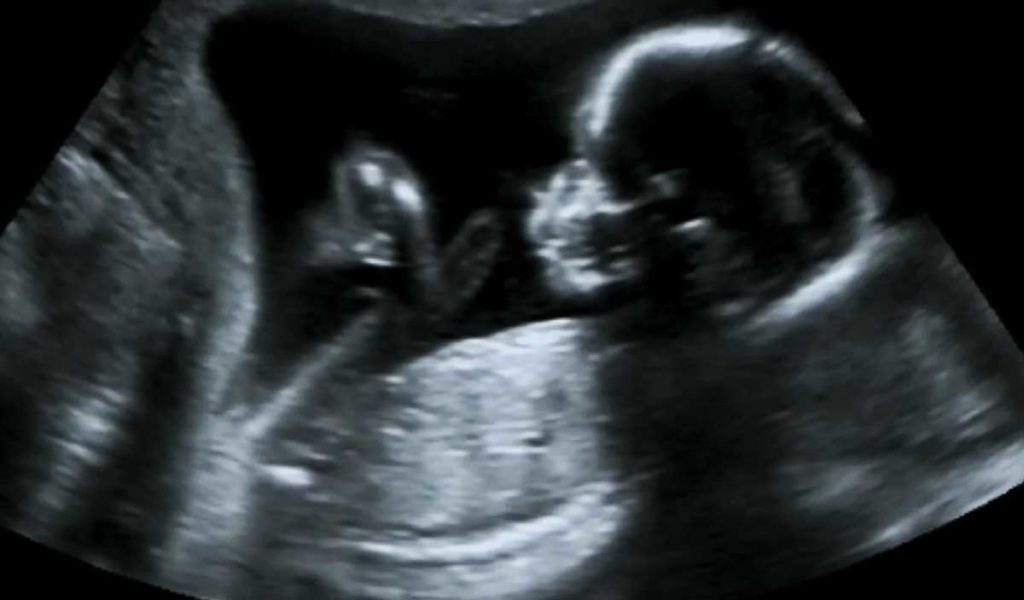

Et puis, lors de la 2e échographie (entre la 20ème et 24ème semaine de grossesse), vous apprenez le sexe de votre bébé. Et ce n’est pas celui que vous espériez.